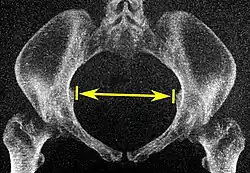

| Pelvic inlet | Transverse diameter of the pelvic inlet |

![]() Coronal plane |

The iliopectineal lines, at widest transverse distance. | 13 to 14.5 cm.[4] |